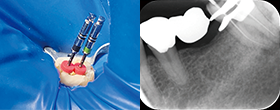

エッジシークエル サファイア.04テーパーを使用した根管形成の作業フロー図※詳細は、添付文書をご確認ください。

穿通

グライドパス形成~根管形成

根管形成完了

• ハンドファイル#10

作業長に到達させた時の抵抗感

• Tight

(きつい)

• Medium

(中くらい)

• Light

(軽い)

作業長に

• 到達する

• 到達

しない

1つ下の

サイズを

用いて

根管形成を

行う

※到達するまで

繰り返す。